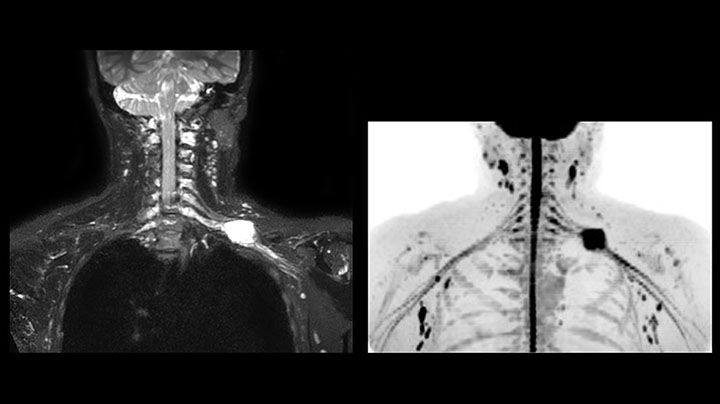

Although the area between the neck and the top of the lung is one of the most difficult areas for MRI, Prodiva 1.5T images show good quality in this 56-year-old male with Pancoast tumor on the right. mDIXON TFE images shows excellent fat suppression in the neck area and the DWI shows almost no distortion.

This patient is a 43-year-old female with a left supraclavicular nerve sheath tumor. The lesion is well visualized on the STIR VISTA images and on the MR neurography using DWIBS. The exam was performed on Prodiva 1.5T.

Acq voxel size 1.2 x 1.3 x 2.4 mm, Recon voxel size 0.7 x 0.7 x 1.2 mm, dS SENSE factor 2, scan time 5:46 min.